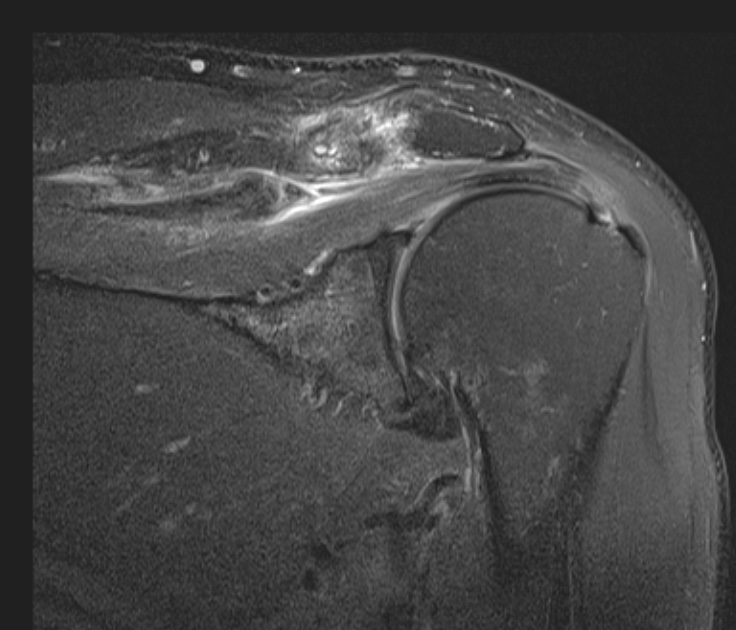

The surgeon said the tear wasnt visible from the articular side and debridement was necessary to reach it from the bursa. The tendon was stuck down and a side to side repair was necessary. You can make out the central defect in the footprint with intact articular and burial surfaces.

I have seen a few of these in Infraspinatus, as per the article linked below, but this was my first in Supraspinatus. Reference article.

Massive interstitial delamination of Supraspinatus with retraction